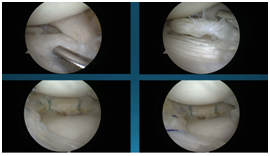

手术是通过关节镜来进行的,是非常微创的手术。一般两个小于1cm的切口就可以解决了。大部分患者仅适用两个小于1cm的切口,而且位于膝眼位置,

不仔细看看不出来。利用关节镜技术把损伤的半月板修整缝合加固。